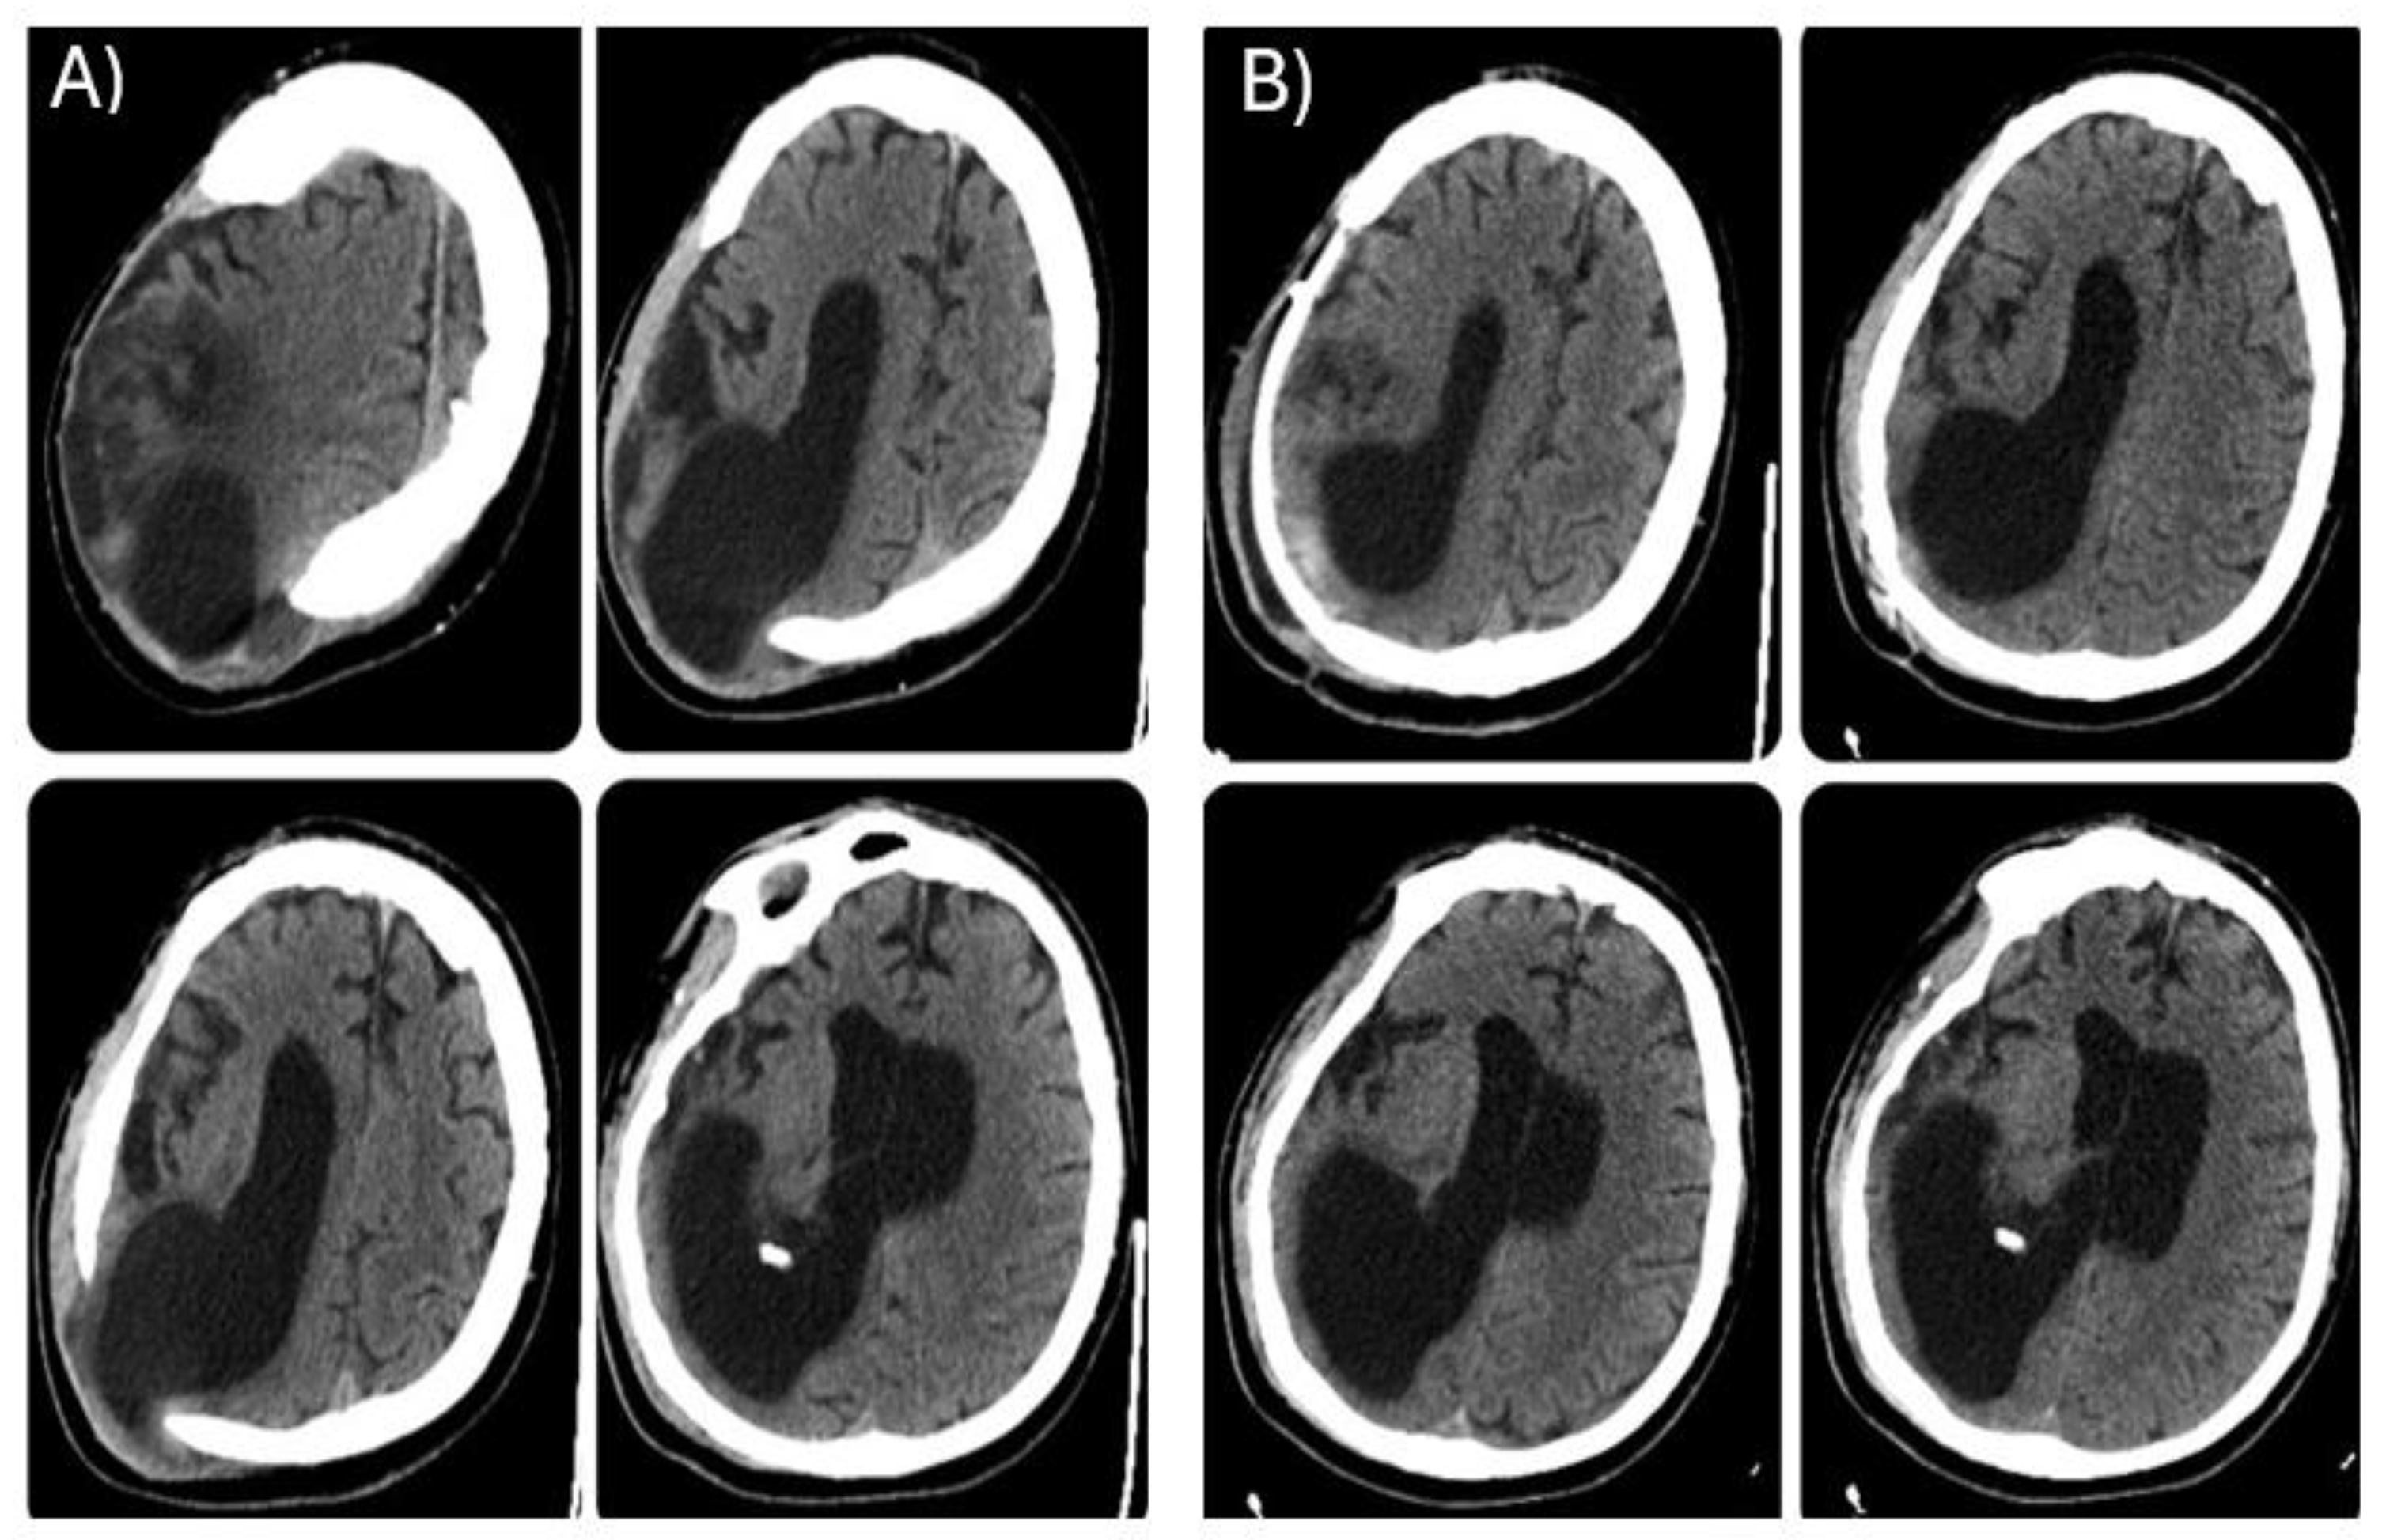

During the LTC stay, the patient was monitored with repeated CT scans. The last brain CT carried out before reconstructive cranioplasty (Figure 2A), showed further right occipital horn enlargement with persistence of brain parenchyma protrusion at the craniectomy site. One month after CP, a CT scan was repeated revealing patches of blood-type hyperdensity in the cortico-subcortical location corresponding to the posterior horn of the right lateral ventricle at the surgical site with persistent significant right ventricle dilatation (Figure 2B).

Figure 2. Brain CT scan, axial view. Left side(A) before cranioplasty, right side(B) after cranioplasty.